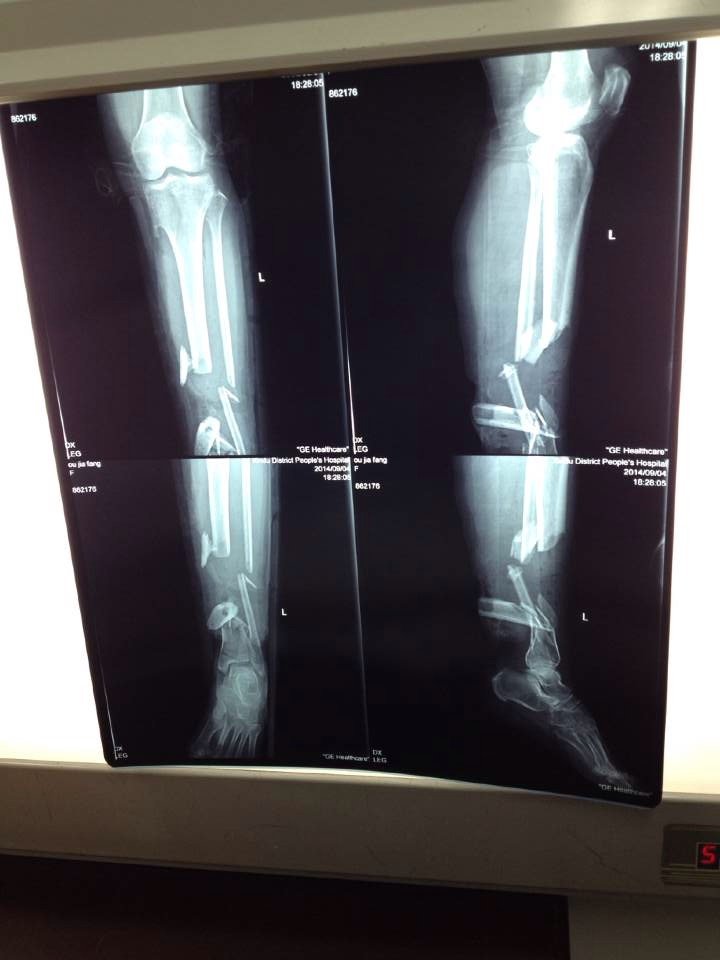

你的情况还是很严重的。粉碎性骨折。建议去去大医院插钢筋试试。

你的情况很严重,粉碎性的骨折,很难接上,只能手术治疗,估计得要放假体,去三级医院看一下吧,资源稍微多一些,由于不能面见患者给予检查,建议先到正规的医院诊断,再根据临床医生的指导进行治疗,严禁自行用药,以免延误病情。